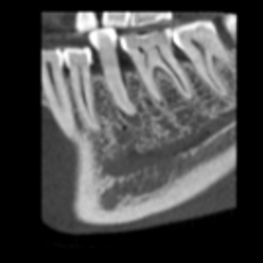

Normalna rozdzielczość przy ultraniskiej dawce

wielkość woksela 200 μm, dawka pacjenta ~20 μSv

Duża szczegółowość, niska dawka